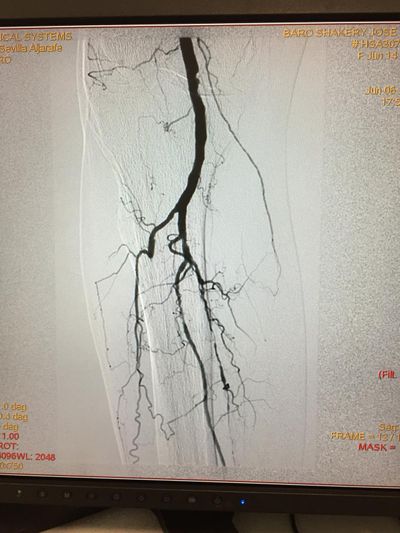

En casos en los que la neuropatía e infección se asocian con isquemia o falta de circulación arterial de la pierna, es necesario una valoración por Cirugía Vascular

para intentar buscar la revascularización mediante by pass o dilataciones endovasculares.